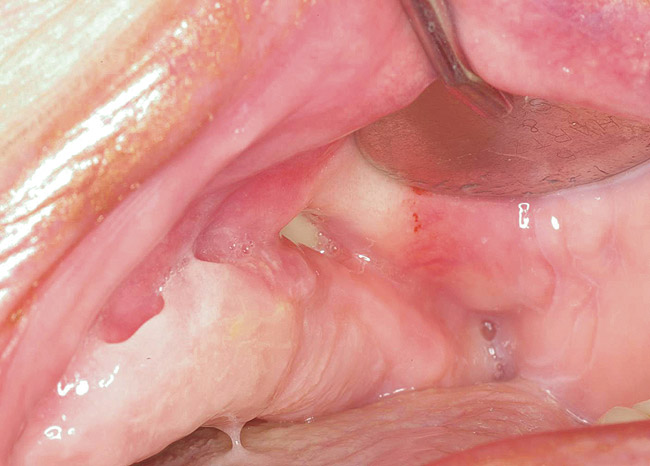

For patients on IV bisphosphonates, after bone is exposed, it is almost impossible to cover.15 Most cases worsen if surgical intervention is performed. Most patients must simply deal with the exposed bone and keep it clean so that bacterial infection does not occur. Figure 2 and Figure 3 show a postmetastatic prostate cancer patient with exposed bone. The treatment plan for this patient was to make a soft-lined denture that would not put pressure on the exposed bone and to check for bacterial infection on a routine basis.

Figure 2  Post-metastatic cancer patient with BRONJ in the lower right quadrant and in the lower left quadrant.

Figure 2

Figure 3  Post-metastatic cancer patient with BRONJ in the lower right quadrant and in the lower left quadrant.

Figure 3